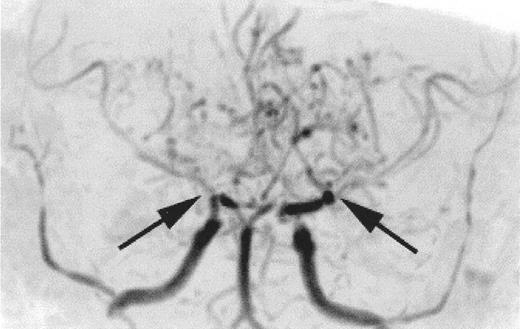

Time-of-flight MR angiogram from a child with sickle cell anemia (SCA) and Moya-Moya.

Severe narrowing of the distal internal carotid arteries and proximal middle cerebral arteries (black arrows) is typical of the intracranial vasculopathy seen with SCA. Prominent lenticulostriate collateral vessels produce the Moya-Moya (“puff of smoke”) pattern seen above the stenoses.

The relationship between SCI and other patterns of brain injury that can be seen in children with SCA is not well defined. In part, this is because SCI can only be identified with surveillance MRI evaluations, which have only recently become routine in some clinical centers. A common finding is cerebral atrophy. This is a non-specific finding that serves as a marker for disease severity in the brain. Another common finding is Moya-Moya, a description that comes from the Japanese for “puff of smoke” because of the angiographic appearance of secondary extensive collateral formation. Figure 2 is a time-of-flight MRI angiogram in a child with SCA and Moya-Moya. The arrows indicate the stenosis/occlusion of the distal internal carotid arteries. The child with SCA and Moya-Moya shown in Figure 3 has an extensive area of cortical infarction corresponding to the distribution of the posterior cerebral artery (arrows) and silent cerebral infarct in the frontal regions.